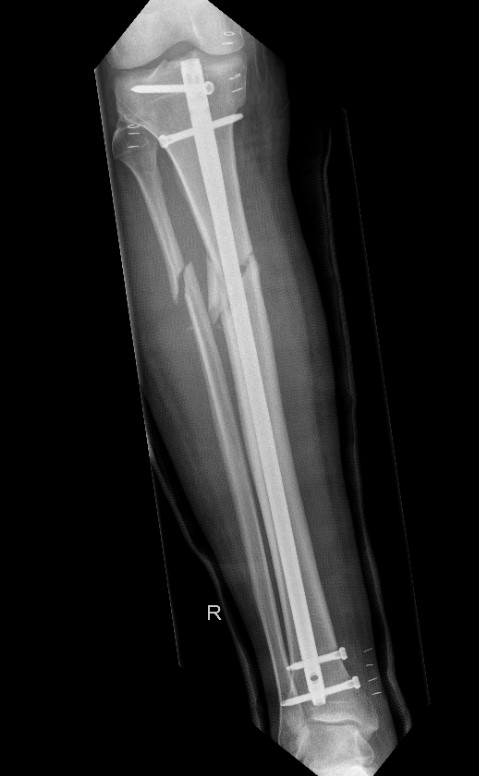

IMN Proximal tibial fractures

Issue

High incidence malunion

- coronal plane valgus

- saggital plane flexion / procurvatum

- posterior translation of distal segment

2. Blocking screws

- also lateral and posterior

- functionally narrow IM canal

- on concave side of deformity at the level of the fracture

- same positions as entry point

- posterior in proximal segment adjacent to fracture

- lateral in proximal segment adjacent to fracture

Smith and Nephew Tibial Meta Nail with Blocking Screws